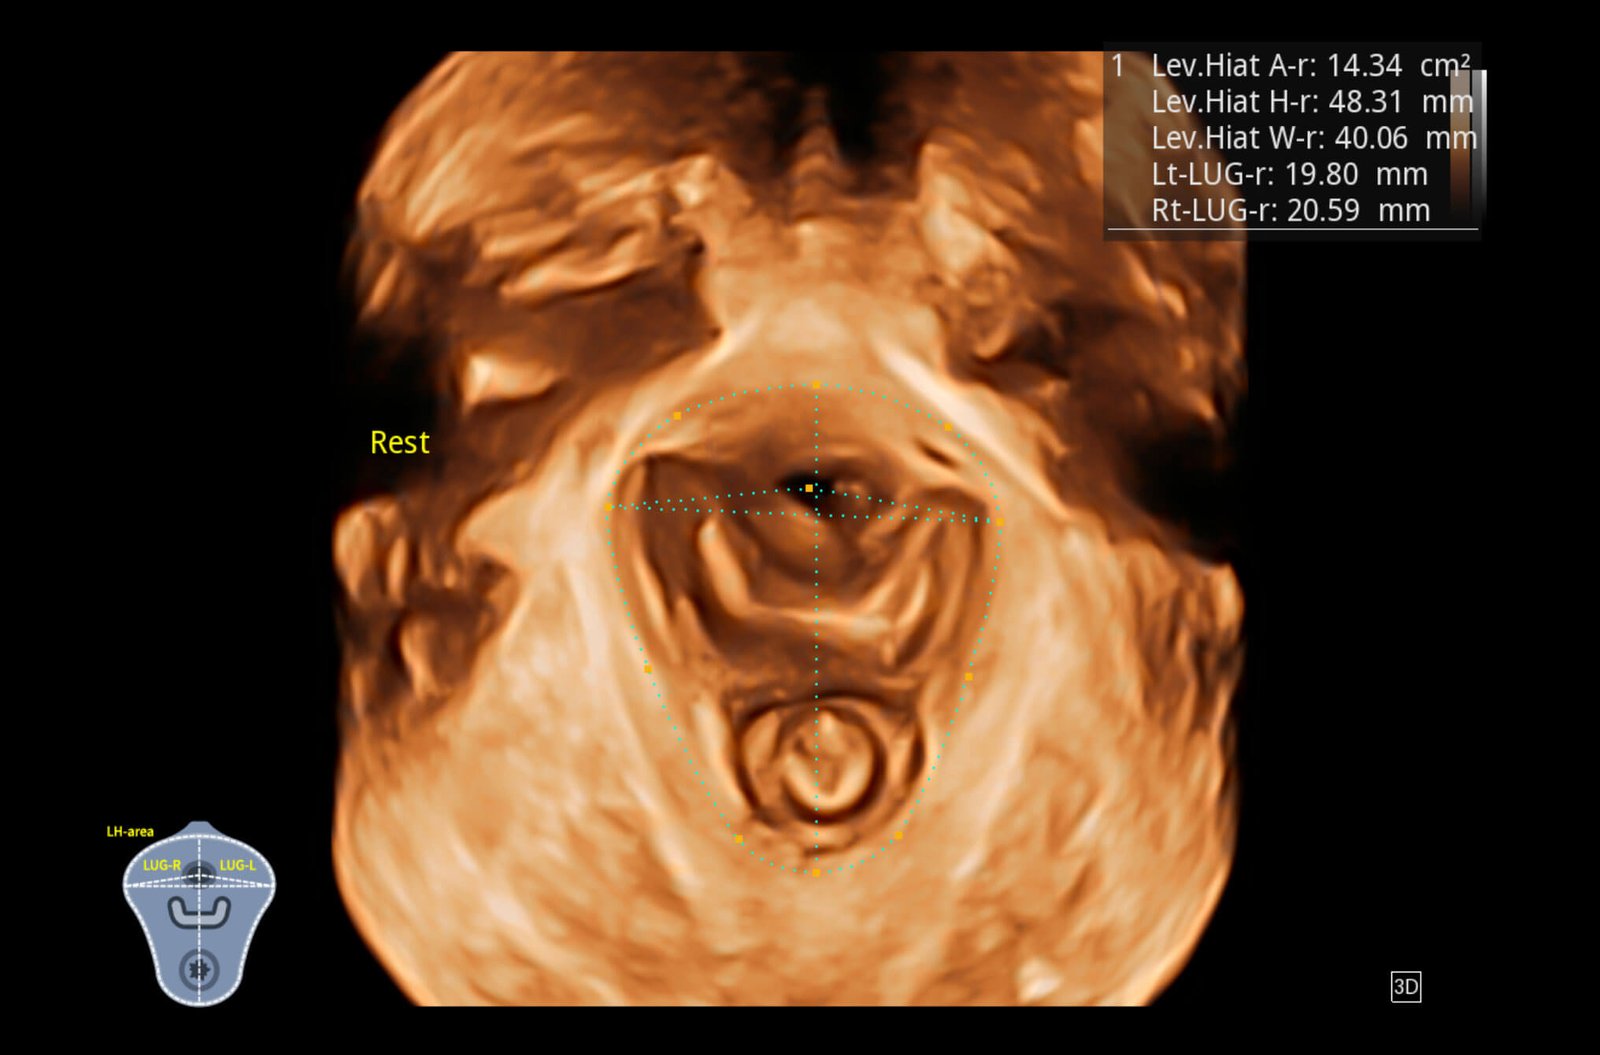

Ultra-light Crafted Volume VC2-9

Reduced weight, ultra-wide bandwidth, exquisite resolution and penetration at high volume rate, VC2-9 is a one-probe-solution throughout nearly the entire pregnancy.